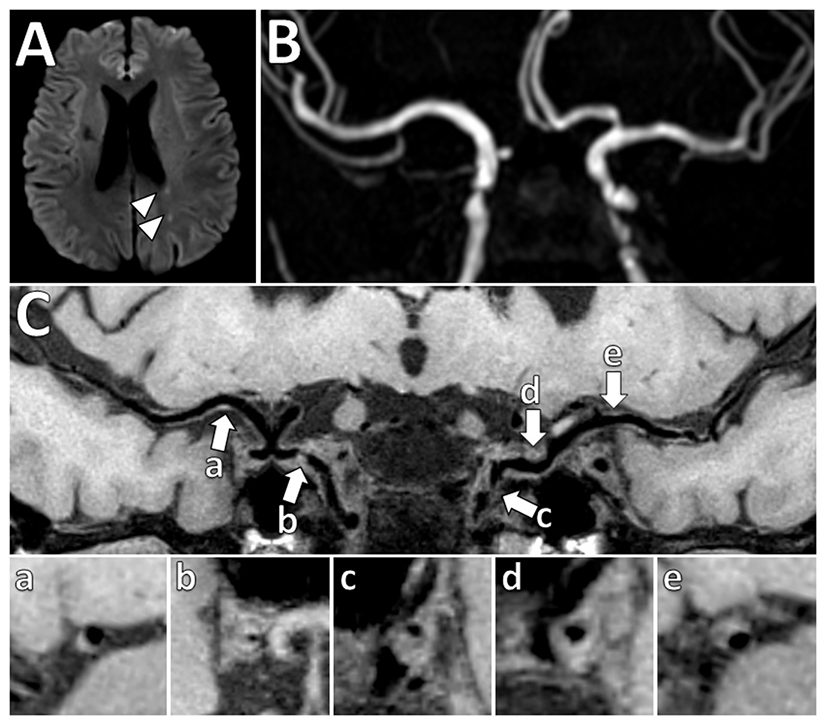

The pattern of wall thickening can be either concentric or eccentric. Per a recent systematic review, the most common definition of identifying intracranial plaque using VW-MRI was focal/eccentric vessel wall thickening (59). Several authors have defined that vessel wall thickening can be considered concentric if it is circumferential and uniform, with the thinnest segment being at least 50% of the thickest segment. On the other hand, vessel wall thickening is considered eccentric if the wall thickening is clearly focal, or when circumferential wall thickening is noted but the thinnest segment of the wall thickening is <50% of the thickest segment (62, 73). Examples of plaque with both eccentric and concentric wall thickening are shown in Figure 5.

Figure 5

Vessel wall thickening and atherosclerosis on VW-MRI in a symptomatic patient. (A) A patient with left parietal lobe acute ischemic infarcts (arrowheads) underwent intracranial VW-MRI. (B) Time-of-flight MRA and (C) intracranial VW-MRI shows multiple intracranial plaques (arrows) that showed both eccentric (a, b, c, e) and concentric (d) vessel wall thickening. The culprit lesion was thought to be the most stenotic lesion (c) in the left internal carotid artery.